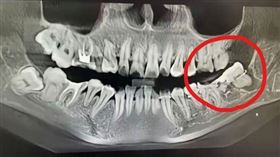

水平智齒不處理恐釀禍! 「3狀況」須就醫

原本一口排列整齊的「微笑曲線」,卻因為智齒的出現都亂...

2024/07/30 14:30